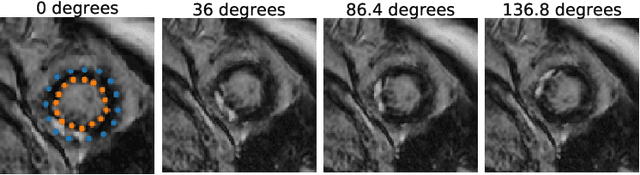

Abstract:Accurate delineation of the left ventricular boundaries in late gadolinium-enhanced magnetic resonance imaging (LGE-MRI) is an essential step for scar tissue quantification and patient-specific assessment of myocardial infarction. Many deep-learning techniques have been proposed to perform automatic segmentations of the left ventricle (LV) in LGE-MRI showing segmentations as accurate as those obtained by expert cardiologists. Thus far, the existing models have been overwhelmingly developed and evaluated with LGE-MRI datasets from single clinical centers. However, in practice, LGE-MRI images vary significantly between clinical centers within and across countries, in particular due to differences in the MRI scanners, imaging conditions, contrast injection protocols and local clinical practise. This work investigates for the first time multi-center and multi-vendor LV segmentation in LGE-MRI, by proposing, implementing and evaluating in detail several strategies to enhance model generalizability across clinical cites. These include data augmentation to artificially augment the image variability in the training sample, image harmonization to align the distributions of LGE-MRI images across centers, and transfer learning to adjust existing single-center models to unseen images from new clinical sites. The results obtained based on a new multi-center LGE-MRI dataset acquired in four clinical centers in Spain, France and China, show that the combination of data augmentation and transfer learning can lead to single-center models that generalize well to new clinical centers not included in the original training. The proposed framework shows the potential for developing clinical tools for automated LV segmentation in LGE-MRI that can be deployed in multiple clinical centers across distinct geographical locations.

Abstract:Accurate segmentation of the cardiac boundaries in late gadolinium enhancement magnetic resonance images (LGE-MRI) is a fundamental step for accurate quantification of scar tissue. However, while there are many solutions for automatic cardiac segmentation of cine images, the presence of scar tissue can make the correct delineation of the myocardium in LGE-MRI challenging even for human experts. As part of the Multi-Sequence Cardiac MR Segmentation Challenge, we propose a solution for LGE-MRI segmentation based on two components. First, a generative adversarial network is trained for the task of modality-to-modality translation between cine and LGE-MRI sequences to obtain extra synthetic images for both modalities. Second, a deep learning model is trained for segmentation with different combinations of original, augmented and synthetic sequences. Our results based on three magnetic resonance sequences (LGE, bSSFP and T2) from 45 different patients show that the multi-sequence model training integrating synthetic images and data augmentation improves in the segmentation over conventional training with real datasets. In conclusion, the accuracy of the segmentation of LGE-MRI images can be improved by using complementary information provided by non-contrast MRI sequences.